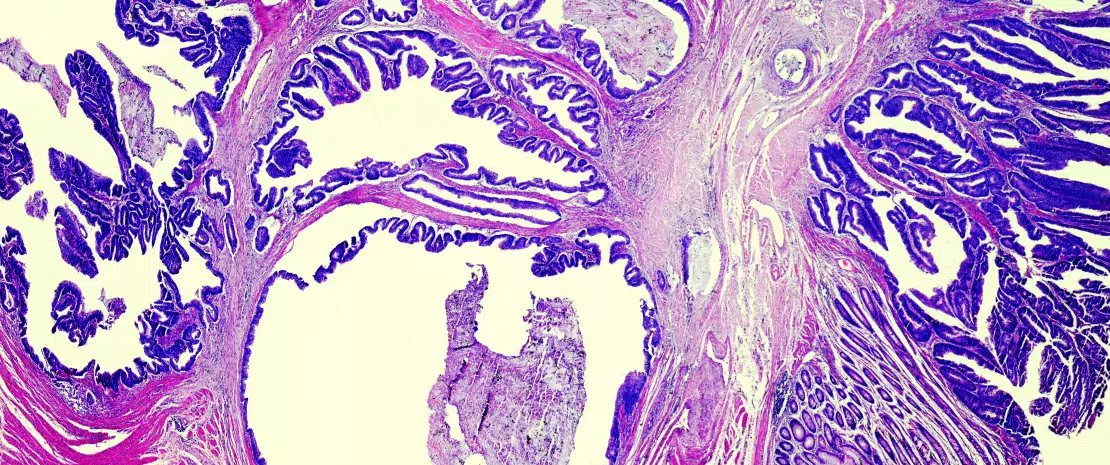

Light microscope section through colon tissue showing an adenocarcinoma.